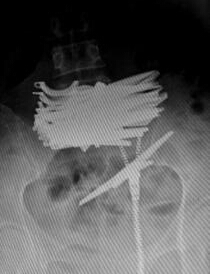

x光片显示,一捆剪刀清晰可见。

5月13日上午,42岁的曲颖(化名)躺在省直中医院普外科的病床上。11日晚上,其因腹痛被路人发现后拨打120,送往医院救治。X光片显示,其中下腹部横亘着一捆剪刀,曲颖称自己为了躲避被抓,便吞下了这些剪刀,大概有10把。

剪刀长约12厘米,需手术取出

当天晚上,省直中医院急诊科对曲颖进行了抢救,随后送往普外科住院治疗,从X光片可见一捆剪刀横亘在其中下腹部,剪刀长近12厘米。医生诊断腹部肠管少量积气,未见明显液气平面和肠管扩张。曲颖身无分文,普外科医生为她进行输液治疗。